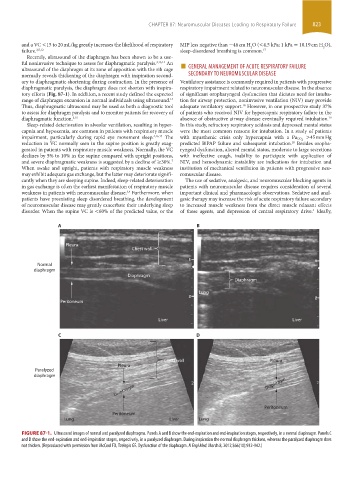

A B

Pleura

Chest wall

Normal

diaphragm

Lung

Peritoneum

Liver Liver

C D

Chest wall Pleura

Paralyzed

Diaphragm Diaphragm

Lung Liver Lung

FIGURE 87-1. Ultrasound images of normal and paralyzed diaphragms. Panels A and B show the end-expiration and end-inspiration stages, respectively, in a normal diaphragm. Panels C

and D show the end-expiration and end-inspiration stages, respectively, in a paralyzed diaphragm. During inspiration the normal diaphragm thickens, whereas the paralyzed diaphragm does

not thicken. (Reproduced with permission from McCool FD, Tzelepis GE. Dysfunction of the diaphragm. N Engl Med. March 8, 2012;366(10):932-942.)